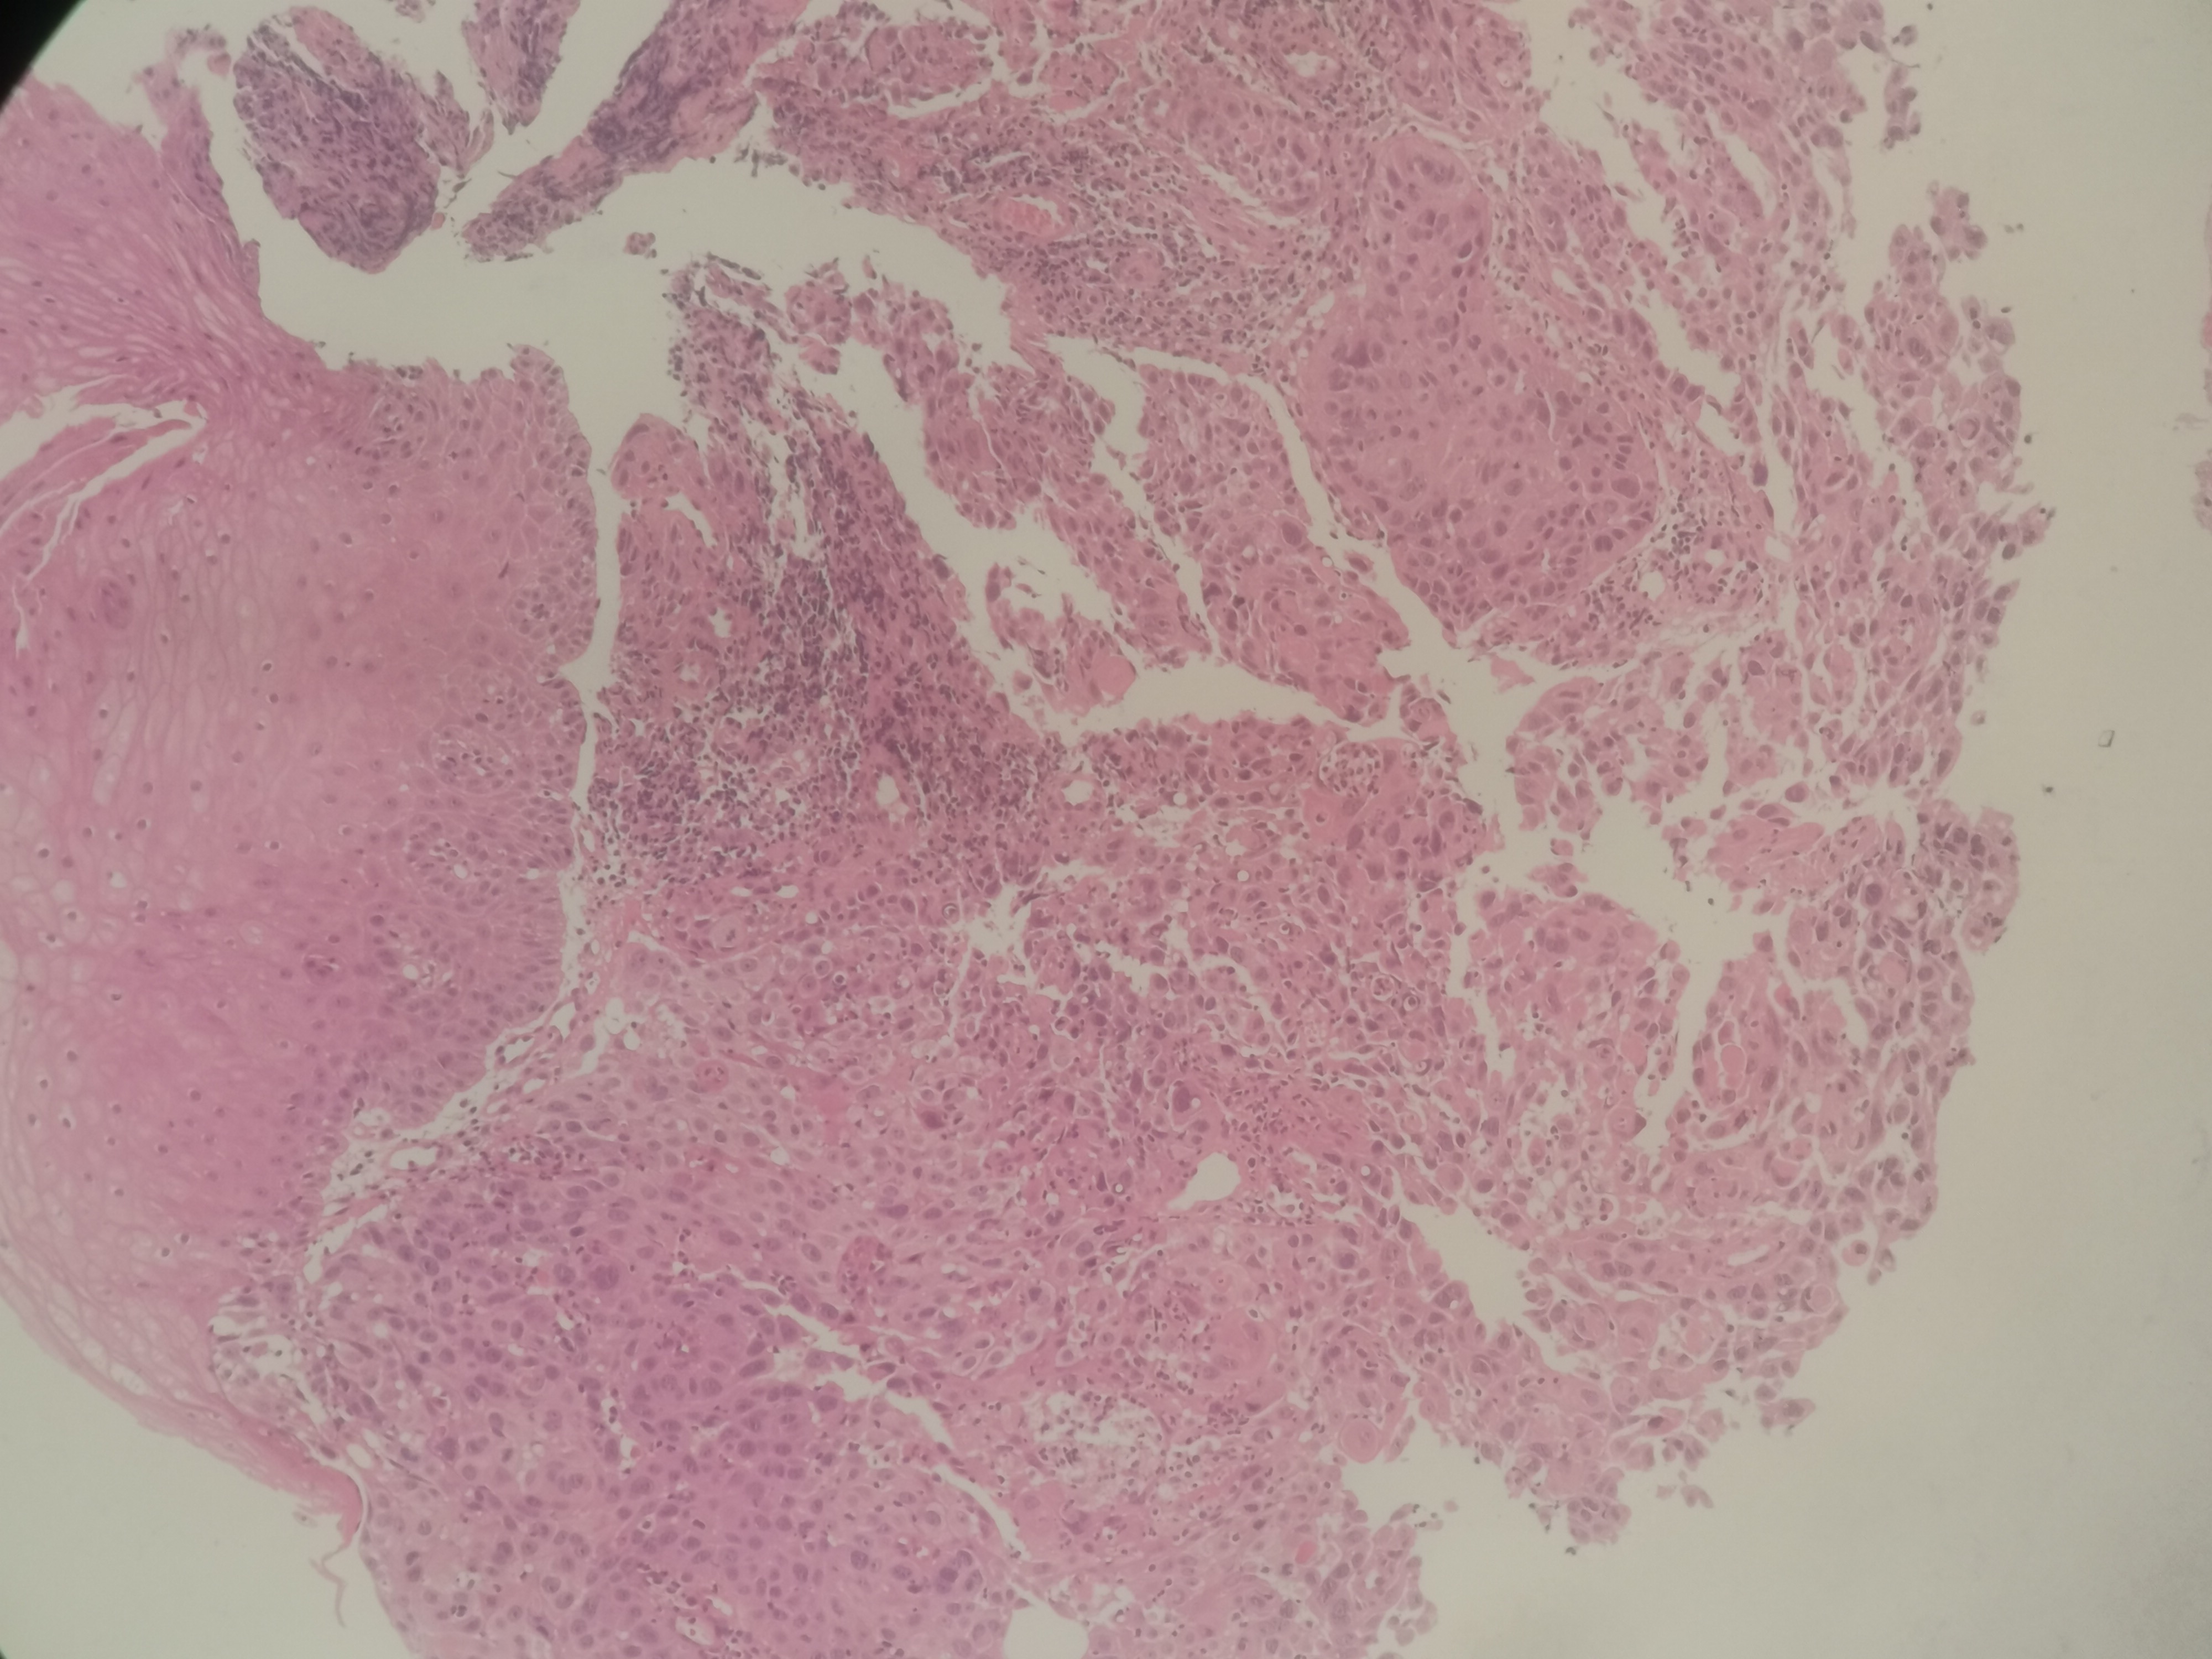

求助,请老师鳞状细胞癌高分化吗?

性别

男

年龄

55岁

临床诊断

食道肿物?

一般病史

食道35~40厘米处不规则增生性肿物,环管腔1/2表面充血、糜烂,质脆,易出血

标本名称

食道活检

大体所见

送检组织0.15x0.1x0.1厘米~0.45x0.3x0.3厘米5块

高分化鳞状细胞癌